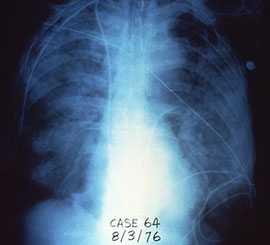

Legionnaires' disease symptoms are similar to other types of pneumonia and it often looks the same on a chest x-ray.